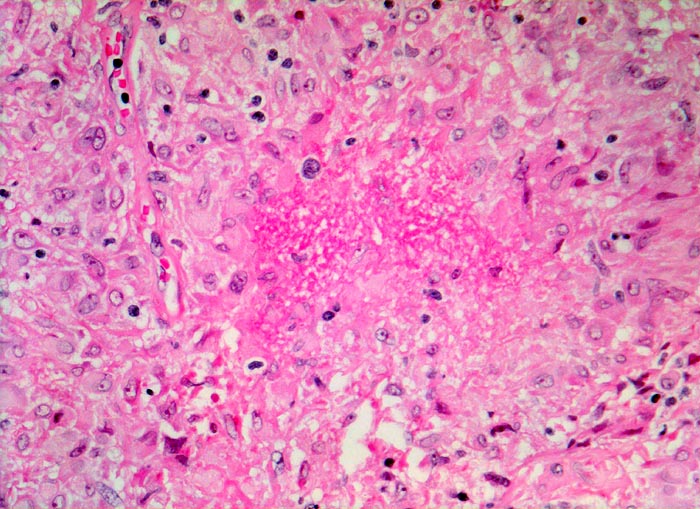

PathoPic – image database / PathoPic ID 4042 - Lymphknotensarkoidose (Morbus Boeck): Granulom mit Nekrose

Lymphknotensarkoidose (Morbus Boeck): Granulom mit Nekrose

Exsudatives Granulom mit zentraler Nekrose (Bildmitte).

Vergrösserte inguinale Lymphknoten bei bekannter Sarkoidose mit Befall der Lungen.

Seltenerweise kann man auch bei einer Sarkoidose verkäsende Granulome nachweisen. Zum histologischen Ausschluss einer produktiven Tuberkulose muss in diesem Fall eine Ziehl-Neelsen-Färbung durchgeführt werden, wobei ein negativer Bakteriennachweis die Tuberkulose nicht ausschliesst.